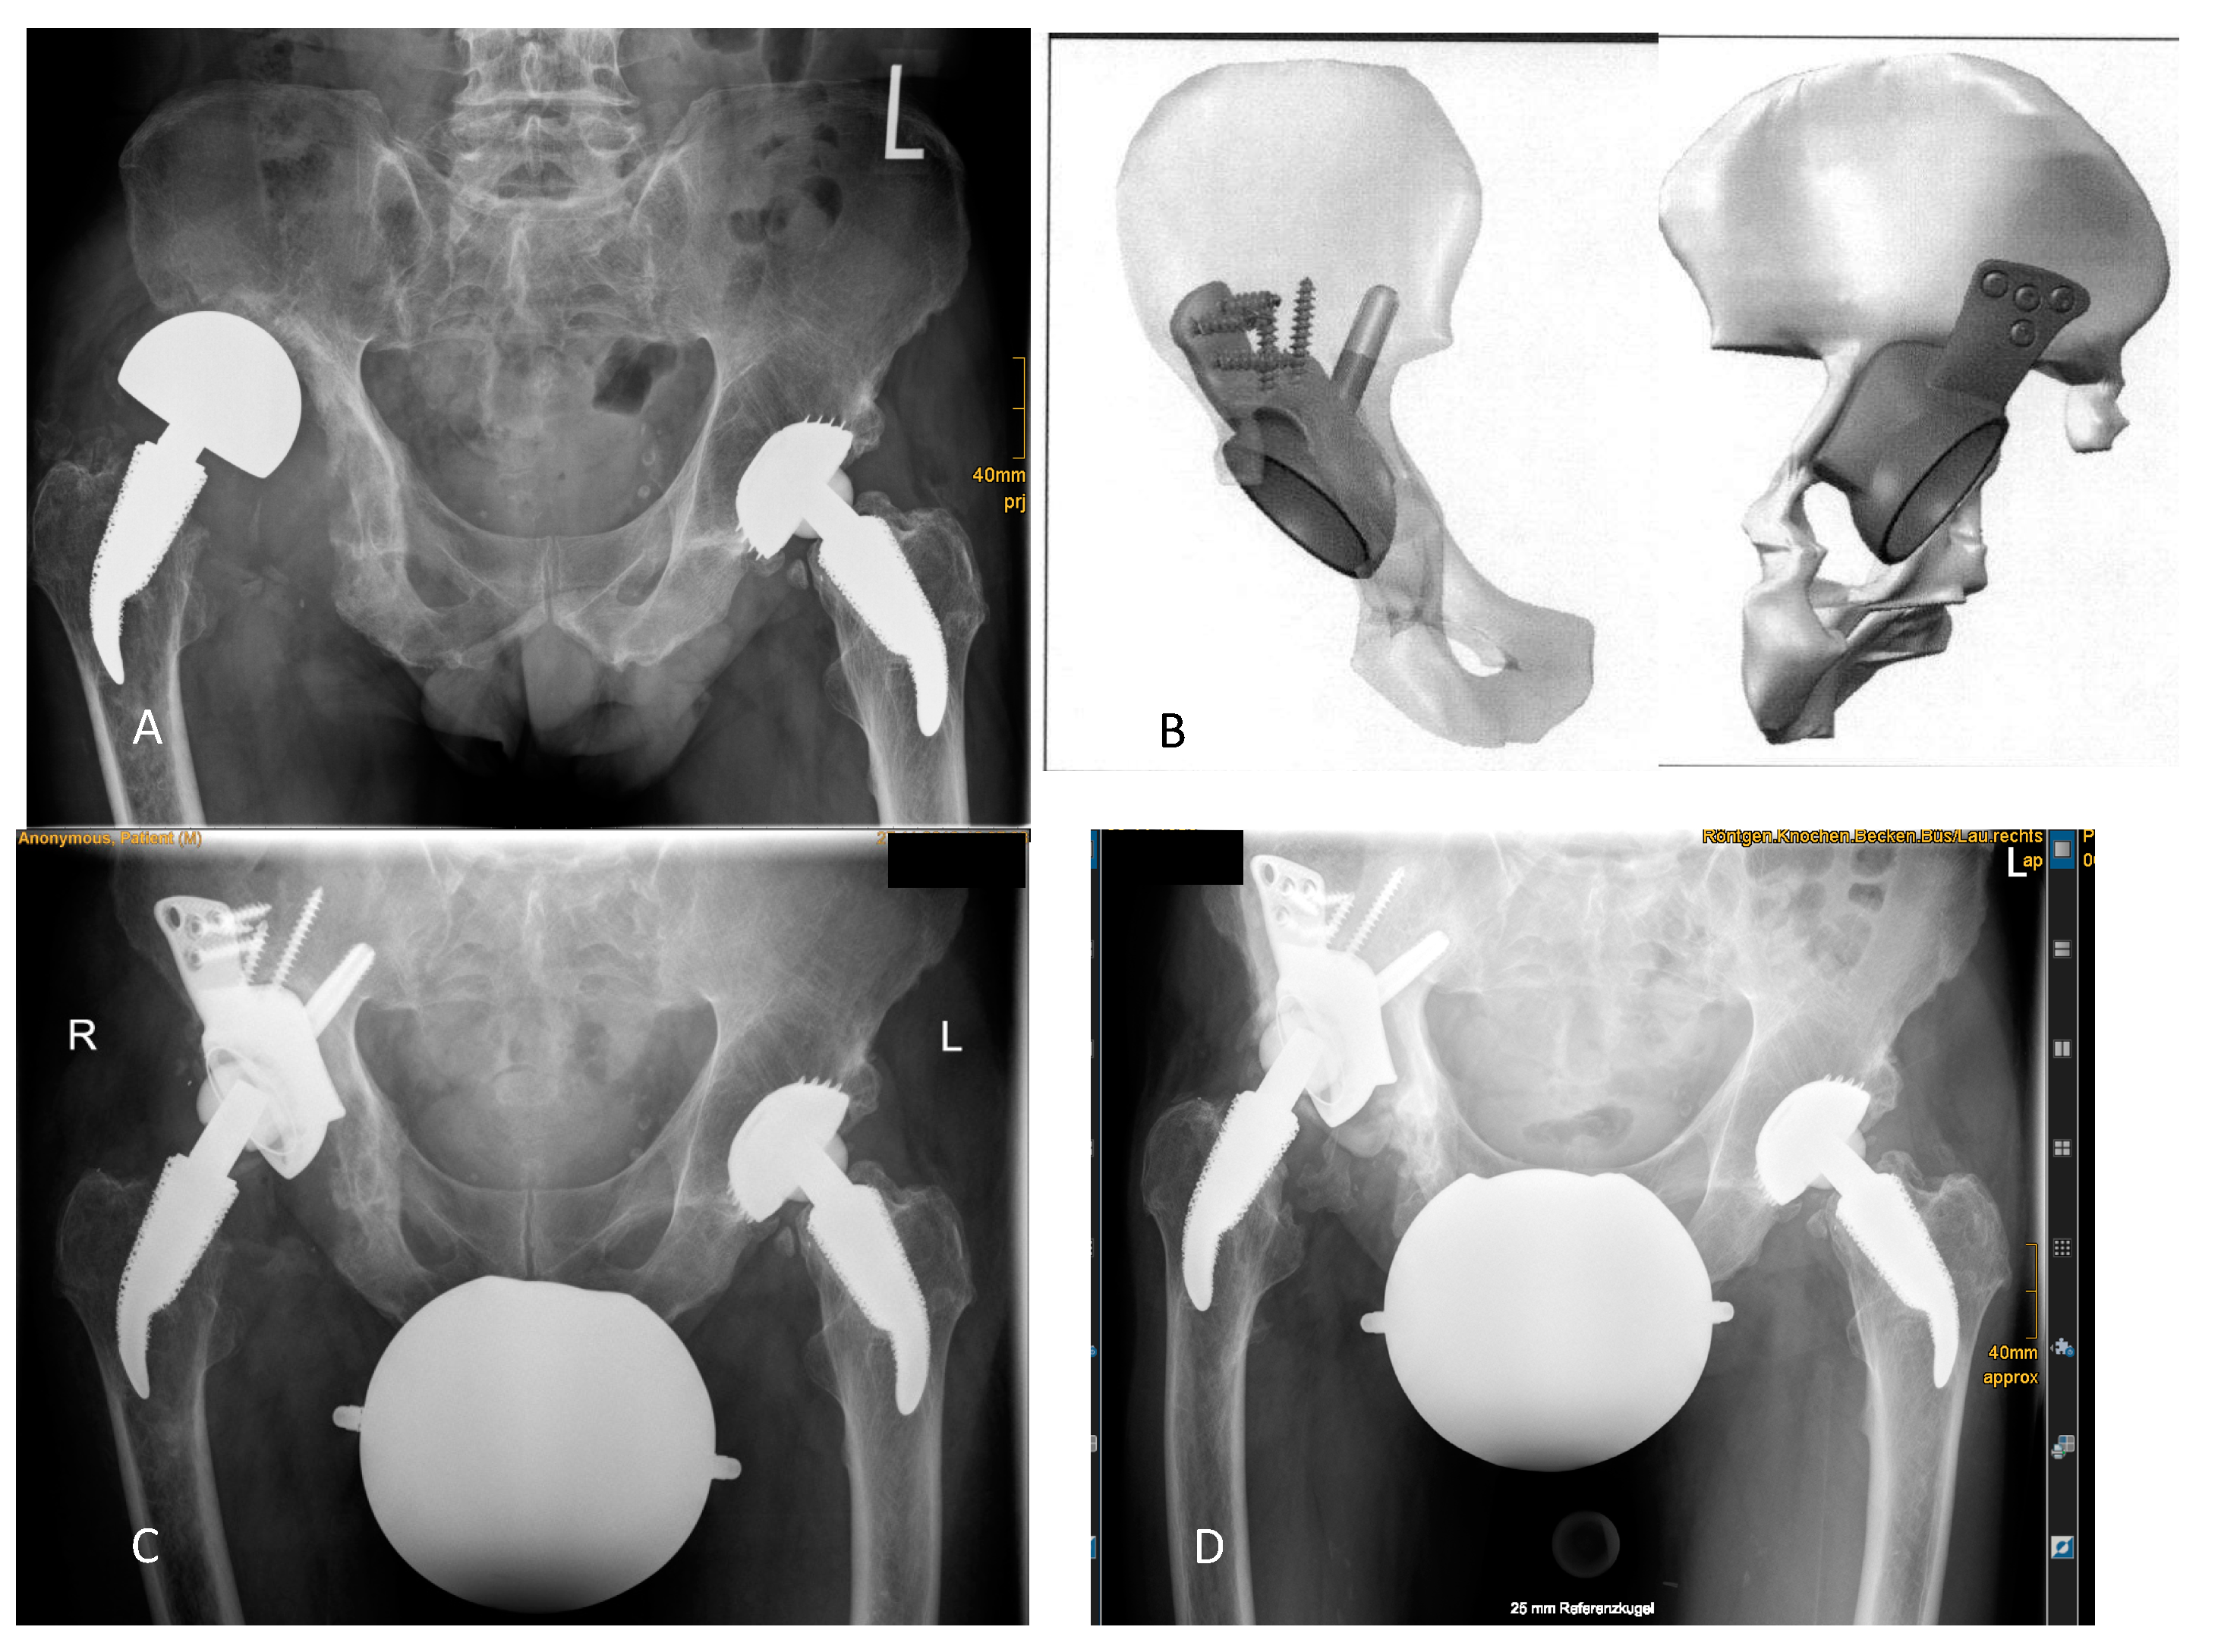

Results of radiographic evaluation are shown in Table 3. Two patients were planned with intentional extra-anatomic reconstruction of COR as depicted in Figure 3 and Figure 4.

For the 10 patients without failure, significant radiolucency lines were found around the socket for one patient, around the acetabular construct for another patient, and around the whole CMAC for the last (Figure 3):

Figure 3. Radiolucency lines without need for revision: (A) Preoperative radiographic situation showed the acetabular “up-and-out” defect after implantation of a large head because of acetabular bone loss. (B) Anterior to posterior (left) and posterior to anterior (right) views show the intended proximalization of the COR in the virtual 3D reconstruction. The cup is not placed at the level of the Kohler’s tear drop. (C) Radiograph after revision and CMAC implantation showed restoration of leg length with a high COR. (D) Significant radiolucency lines developed around the whole implant at 3 years of follow-up. Although implant migration cannot be excluded, the patient was not revised because he reported daily walks of up to 10 km supported by a cane. Thus, this case was not considered a failure.